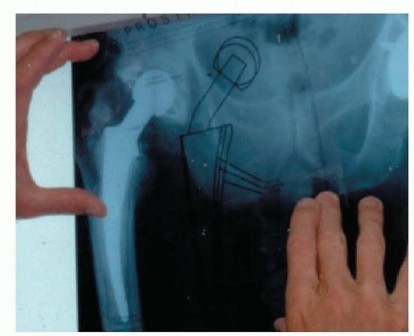

Standard orthogonal radiographs (Anteroposterior pelvis, AP and lateral of the affected hip) are scrutinized for signs of component loosening, endosteal scalloping, or periosteal reaction. Computed Tomography (CT) is invaluable for assessing acetabular bone loss (evaluating the integrity of the anterior and posterior columns, medial wall, and superior dome) and planning for augments or custom triflange constructs.

Preoperative templating must account for the anticipated bone loss following explantation. The surgeon must have a comprehensive armamentarium available, including explantation tools (trephines, flexible osteotomes, ultrasonic cement removal devices), various spacer molds, and revision implant systems (modular fluted tapered stems, highly porous jumbo cups).